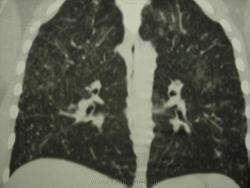

девушка 1985 г.р. дообследована после профилактической флюорографии, на КТ написали гистиоцитоз. Диагноз пока не подтвержден. Жалоб не предъявляет, курит в течение 8-9 лет. консультирована у фтизиатров, свою патологию они исключили.

На мой взгляд, выражены два компонента:

- преимущественно мономорфная диссеминации;

- интерстициальный компонент.

Но, КТ, по всей видимости, свидетельствует, именно, о диффузности процесса, с некоторым превалированием в отдельных отделах.

Изменения диффузны. По rg более выраженны в нижних отделах, за счет марсива тканей. Ждем анализ мокроты и промывных вод.

Очень на то похоже, что аналогия..."Более 90% больных гистиоциозом-Х (Лангергасоклеточным гистиоцитозом) - курильщики"...